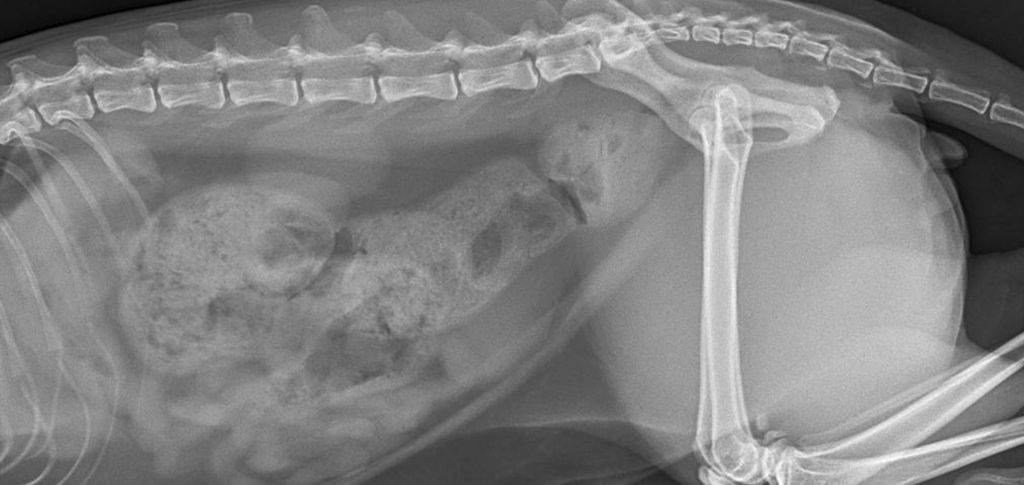

(кошка 7 лет: в течение 7 дней трудности с дефекацией, отсутствие стула в течение последних 4-х дней)

Основной метод диагностики копростаза – это рентген брюшной полости. Рентгенография позволяет определить наличие переломов, аномалий в строении, наличие инородных тел в просвете кишки, визуализировать рентгеноконтрастные новообразования в брюшной полости и кишечнике.